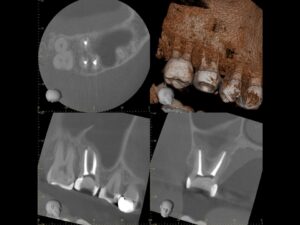

同CT画像。上顎洞のX線不透過部は消失し、上顎洞炎が治癒しているのが分かる。